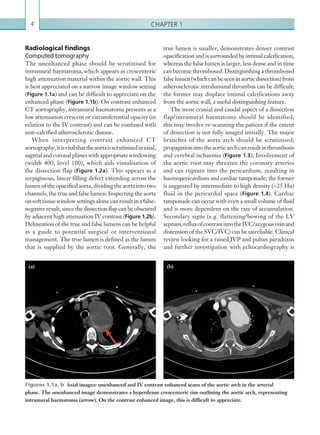

The unenhanced phase should be scrutinised for

intramural haematoma, which appears as crescenteric

high attenuation material within the aortic wall. This

is best appreciated on a narrow image window setting

(Figure 1.1a) and can be difficult to appreciate on the

enhanced phase (Figure 1.1b). On contrast enhanced

CT aortography, intramural haematoma presents as a

low attenuation crescent or circumferential opacity (in

relation to the IV contrast) and can be confused with

non-calcified atherosclerotic disease.

Figures 1.1a, b  Axial images: unenhanced and IV contrast enhanced scans of the aortic arch in the arterial

phase. The unenhanced image demonstrates a hyperdense crescenteric rim outlining the aortic arch, representing

intramural haematoma (arrow). On the contrast enhanced image, this is difficult to appreciate.

(a) (b)